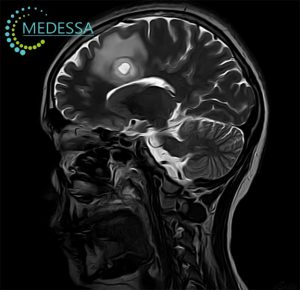

МРТ – найефективніший метод дослідження стану мозку. Він не лише безпечний і неінвазивний, а й надає детальну та точну інформацію, без впливу шкідливого опромінення, на відміну від рентгену чи КТ. МРТ голови дозволяє оцінити всі структури мозку, включаючи судини, мозкові оболонки та нервові корінці.

Цей метод дозволяє своєчасно виявляти різні захворювання, такі як пухлини, метастази, запальні процеси, дегенеративні зміни, деформації та інші патології, що дає змогу лікарям поставити точний діагноз і призначити ефективне лікування.

Для виявлення навіть незначних змін застосовуються 3D-послідовності та зрізи з високою роздільною здатністю.

Як результат, лікар отримує максимально точну інформацію про патології на ранніх стадіях, включаючи пухлини, за короткий час. Загальний час сканування голови без контрасту займає близько 10-15 хвилин.